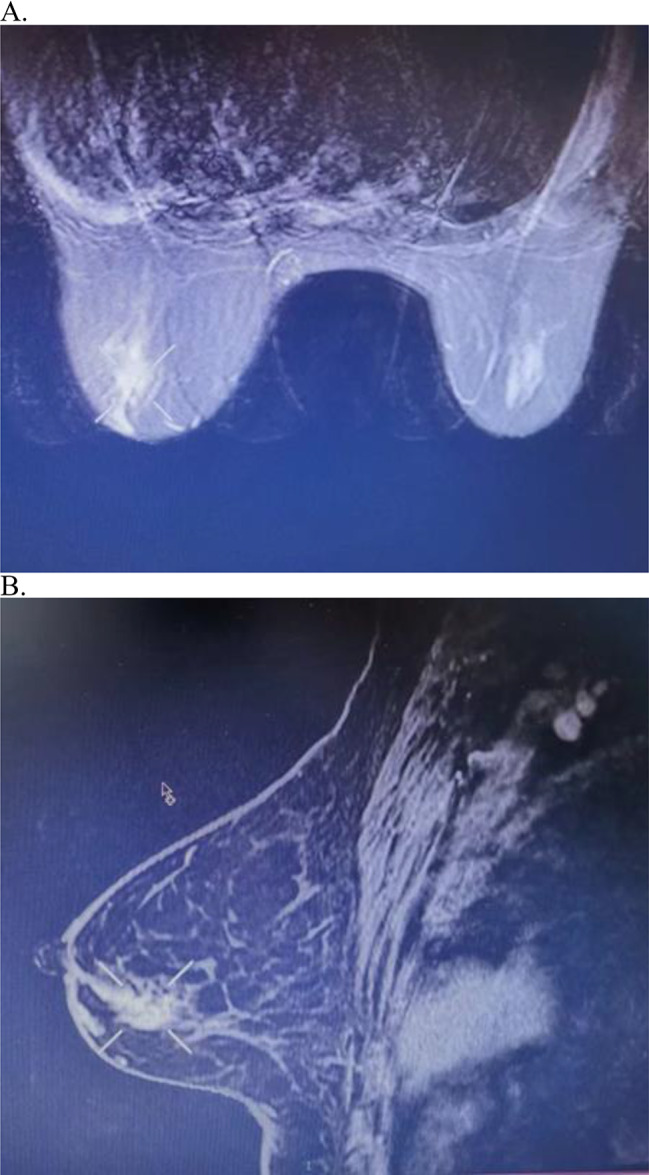

36 months after niraparib treatment, the patient noticed a palpable mass in the left breast. The mass in the left breast and presumed regional lymph nodes in the left axilla were palpable on physical examination. Mammography revealed fine pleomorphic calcifications in the left breast. There was a 1.1 cm × 3.0 cm sized irregular, segmental contrast-enhanced mass in the lower quadrant of the left breast on magnetic resonance imaging (MRI). (Fig. 2) A core needle biopsy of the suspicious breast and left axillary masses was performed under ultrasound (US) guidance. Biopsy results of the breast lesion revealed grade II invasive ductal carcinoma (IDC), which was positive for estrogen receptor (ER, 90%) and Ki-67 (30%), and negative for progesterone receptor (PR) and human epidermal growth factor receptor 2 (HER2). Contrast-enhanced chest, abdominal, and pelvic computed tomography (CT) revealed no distant metastases.

Fig. 2.

MRI scanning of the left breast